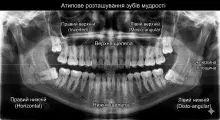

треті моляри